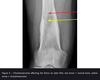

- Routine bloods (FBC, CRP, ESR) - Blood cultures - Plain film radiographs (see image) **- Definitive diagnosis is MRI** **- Gold standard is from culture from bone biopsy** at debridement